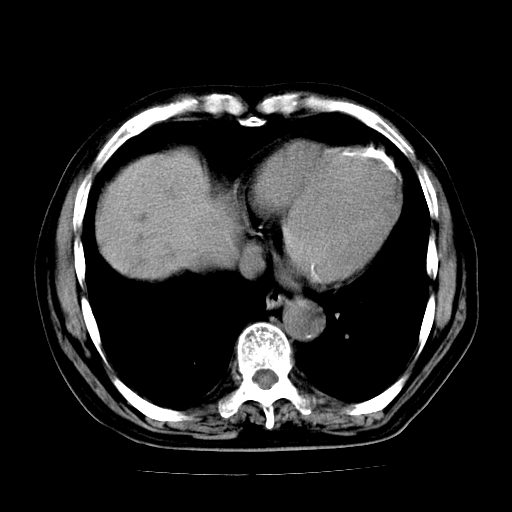

标题: CT25226:男,71岁,皮肤黄染四天。 [打印本页]

男,71岁,皮肤黄染四天。

肝内外胆管及胆总管上段扩张,考虑为梗阻所致,建议mrcp检查。

考虑胆总管癌并肝内外胆管扩张。

胰腺上端胆总管内见软组织影,强化不明显,结合临床,还是考虑低位梗阻性黄疸,胆总管癌可能性大